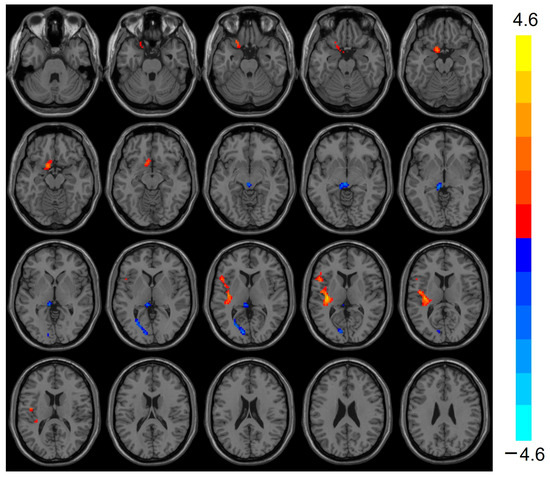

VMHC was elevated (t = 3.803, p < 0.001) in the bilateral Cerebellum_Crus1 of the heart transplant group, while VMHC was reduced (t = −3.424, p < 0.001) in the bilateral calcarine, as shown in Table 3 and Figure 2.

Figure 2.

VMHC values were elevated in the heart transplantation group in bilateral Cerebelum_Crus1 (red), whereas they were reduced in bilateral calcarine (blue). Color bars are t-values. VMHC, voxel-mirrored homotopic connectivity.

VMHC is a validated rs-fMRI evaluation method for quantifying the functional connectivity between the two cerebral hemispheres and is one of the most prominent features of the brain’s basic functional architecture. In pathological states, altered communication between the two cerebral hemispheres can significantly impact cognition and behavior [28]. In this study, VMHC was elevated in the bilateral Cerebellum_Crus1 and decreased in the bilateral calcarine in the heart transplant group. Decreased VMHC in the bilateral calcarine, a primary visual cortex, may indicate disrupted visual information processing, potentially explaining visuospatial deficits in patients. An increasing number of studies recognize that the cerebellum is not only involved in maintaining body balance, motor coordination, and eye movements [29] but also plays a significant role in sensory, cognitive, and emotional learning and regulation [30]. Elevated VMHC in the Cerebellum_Crus1 might indicate maladaptive plasticity in chronic cognitive impairment. Many studies have used fMRI to map motor and non-motor task processes and resting-state networks in the human cerebellar cortex [31]. Pagen et al. found that the functional connectivity of the cerebellum to the brain’s default mode network (DMN) was generally reduced in patients with amnestic mild cognitive impairment (MCI) [32]. The DMN is primarily responsible for the body’s cognitive control in the resting state and maintains inward thinking activity. In patients with Alzheimer’s disease, the DMN is initially disrupted by amyloid deposition caused by the disease process [33]. Both the cerebellum and the prefrontal lobe belong to the DMN. The reduced ReHo in the prefrontal lobe and elevated VMHC in the cerebellum in this study suggest that the DMN is damaged in heart transplant patients.